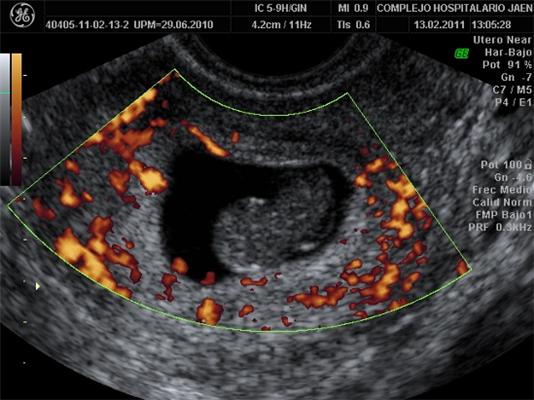

This is an ultrasound image of a spontaneous abortion.(Photo Credit: University of Granada)